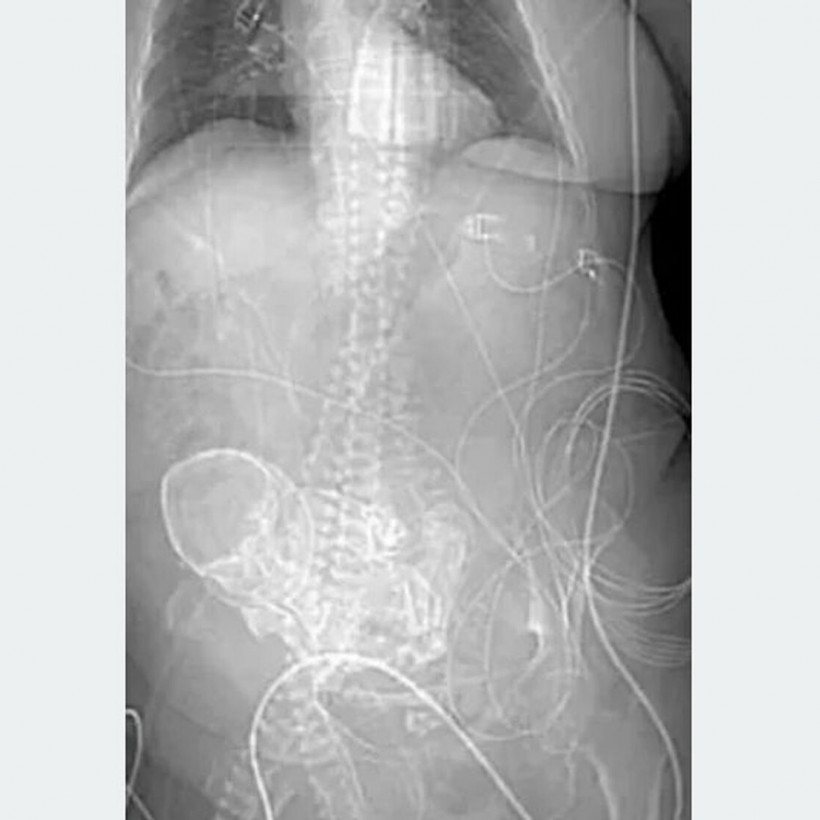

Μια 81χρονη γυναίκα στη Βραζιλία πέθανε μετά από επέμβαση αφαίρεσης ενός σπάνιου «πέτρινου μωρού» που βρισκόταν στο σώμα της για πάνω από μισό αιώνα.

Ήταν το αποτέλεσμα ενός σπάνιου τύπου εξωμήτριας εγκυμοσύνης, γνωστής ως λιθοπεδίου, όπου το έμβρυο πεθαίνει αλλά δεν μπορεί να απορροφηθεί εκ νέου από το σώμα της μητέρας.

Αντίθετα, το νεκρό έμβρυο συγκρατείται στην κοιλιακή κοιλότητα, σχηματίζοντας ένα περίβλημα ασβεστίου γύρω του. Η τομογραφία λήφθηκε αφού μεταφέρθηκε επειγόντως στο Περιφερειακό Νοσοκομείο Ponta Pora στην κεντροδυτική πολιτεία Mato Grosso do Sul της Βραζιλίας με γενικευμένη λοίμωξη.

Πριν από την ανακάλυψη σοκ, οι ειδικοί υποψιάζονταν ότι είχε καρκίνο.